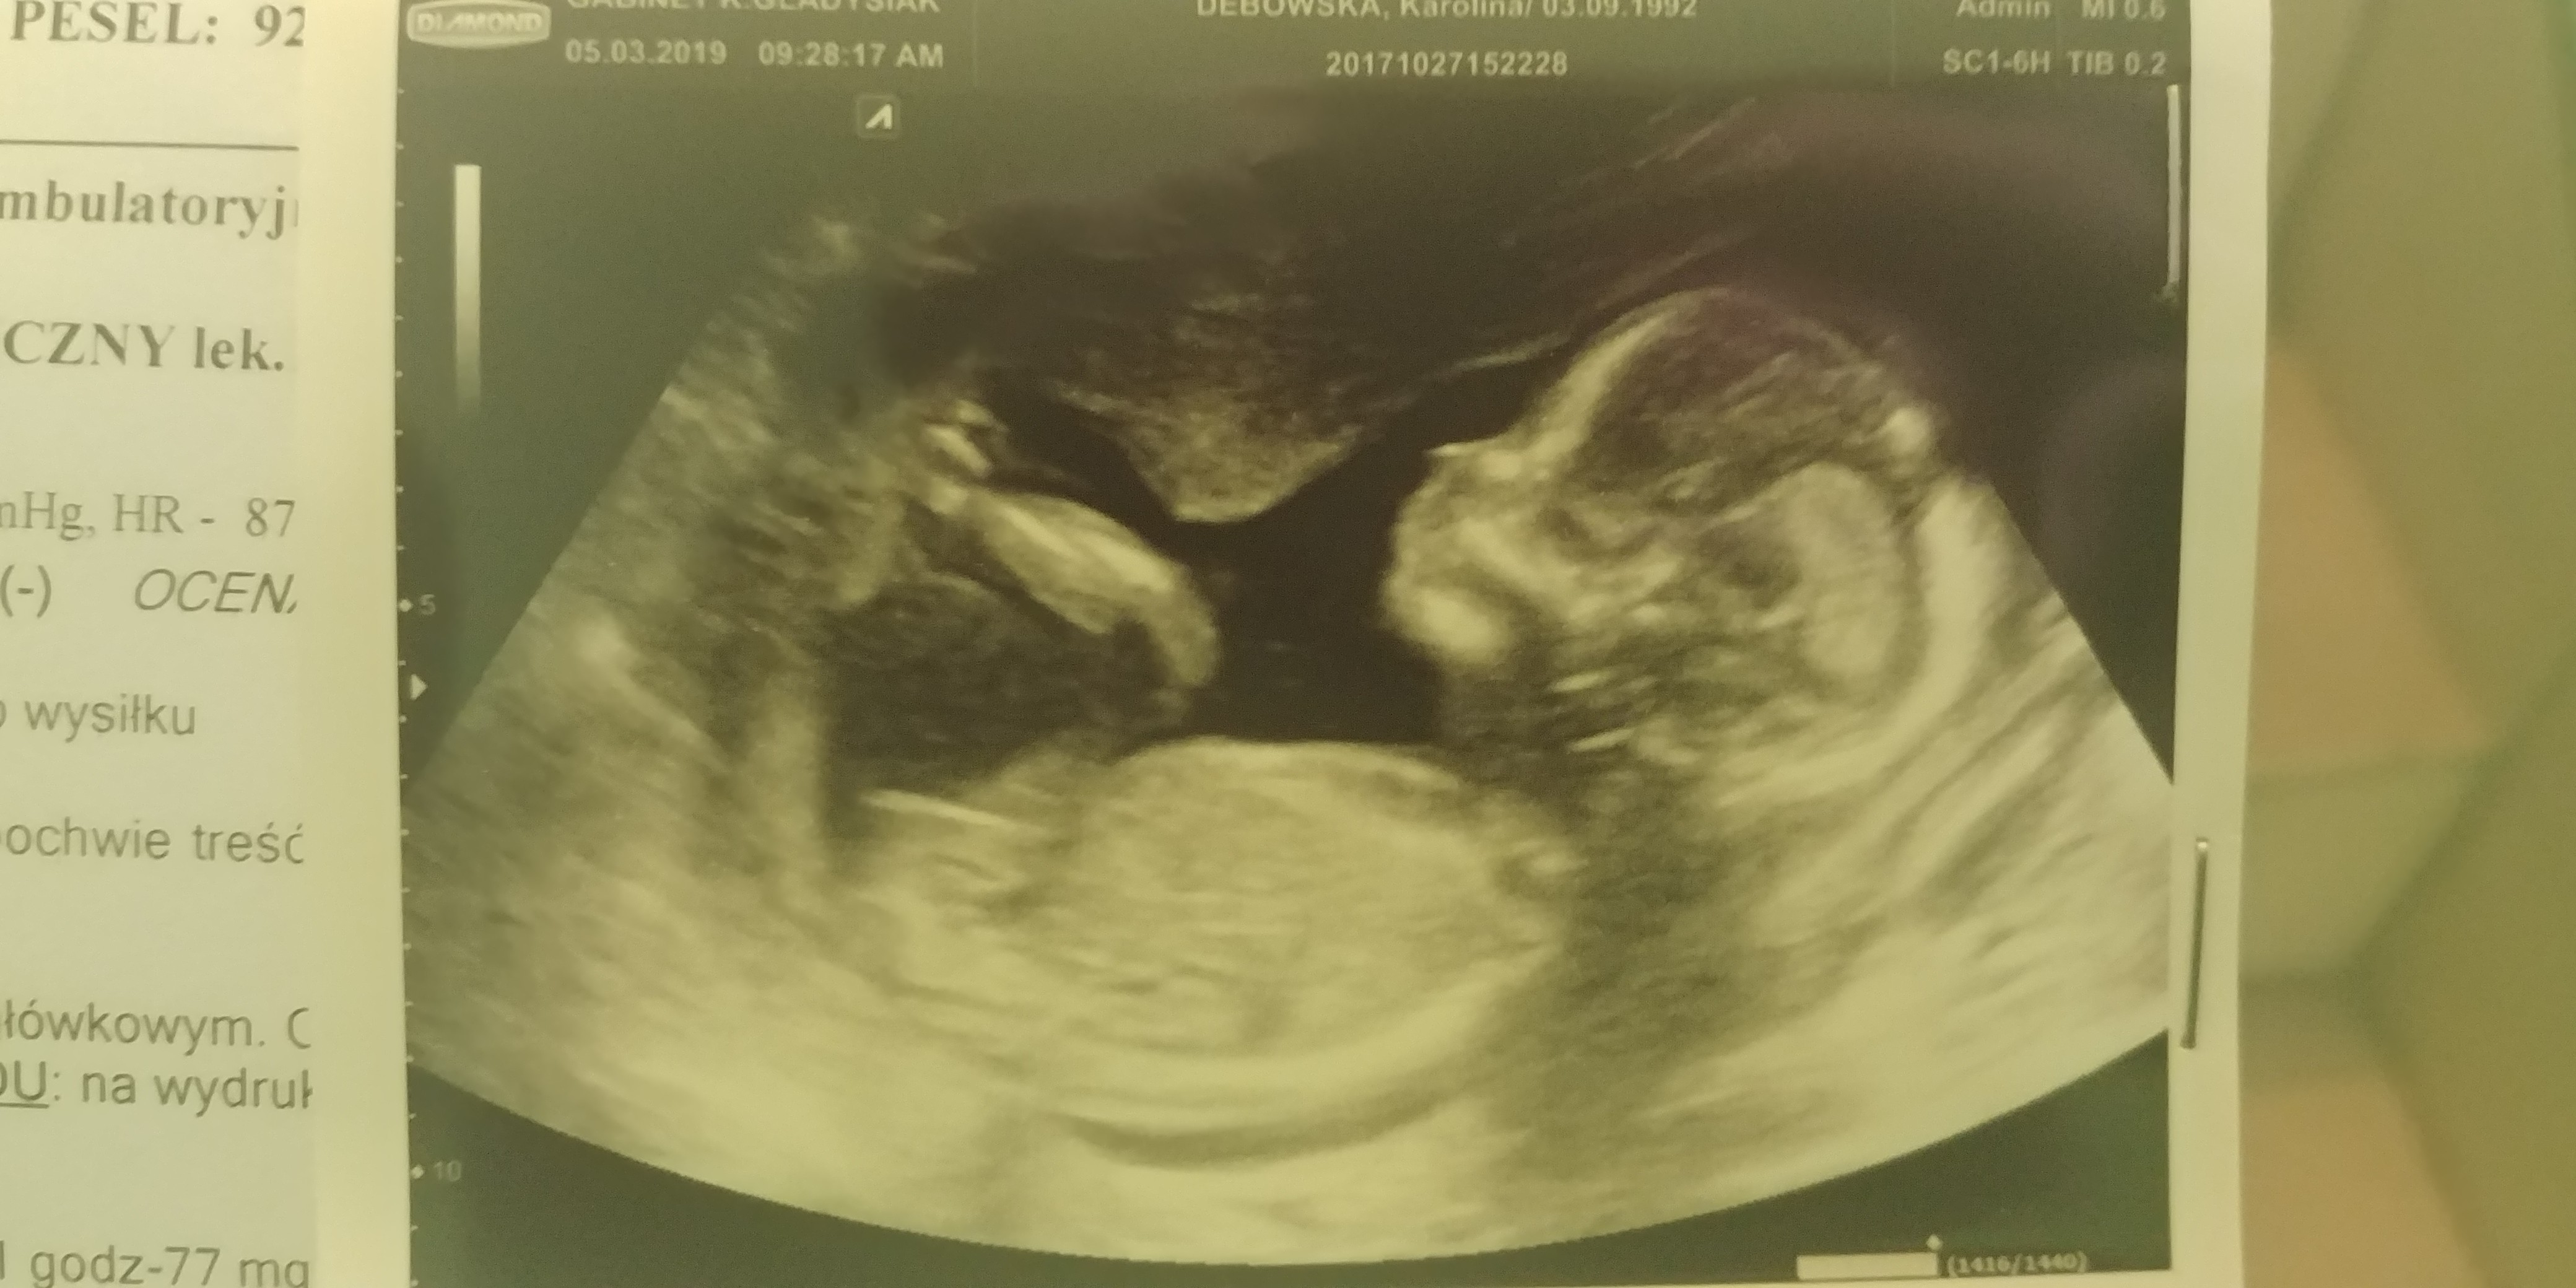

Hej, dziewczyny byłam ma prenatalnych i lekarz powiedzial ze na 90 % chlopak,później bylam u swojego gin i ze tez chlopak. Wczoraj bylam i juz mowi ze dziewczynka.. Mam tylko dwa zdjęcia niestety.

Załączniki

• received_255891791983613.jpeg

received_255891791983613.jpeg

191,7 KB · Wyświetleń: 562

• 20190305_093755.jpg

20190305_093755.jpg

1,1 MB · Wyświetleń: 555